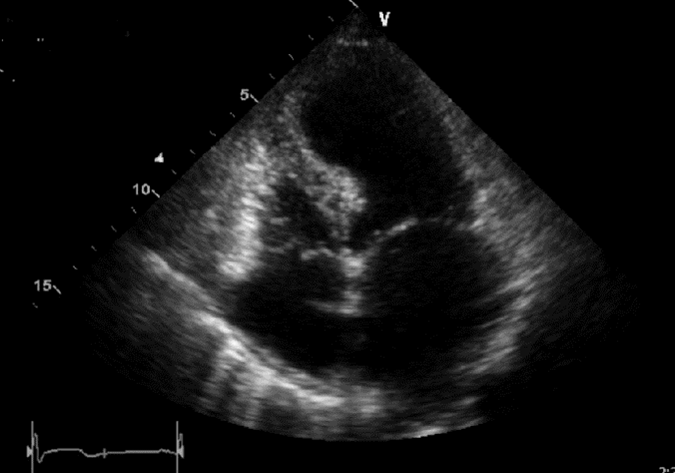

- Apical wall motion abnormality (apical ballooning)

- Possible apical thrombus.

Apical ballooning in patient with Takotsubo Cardiomyopathy